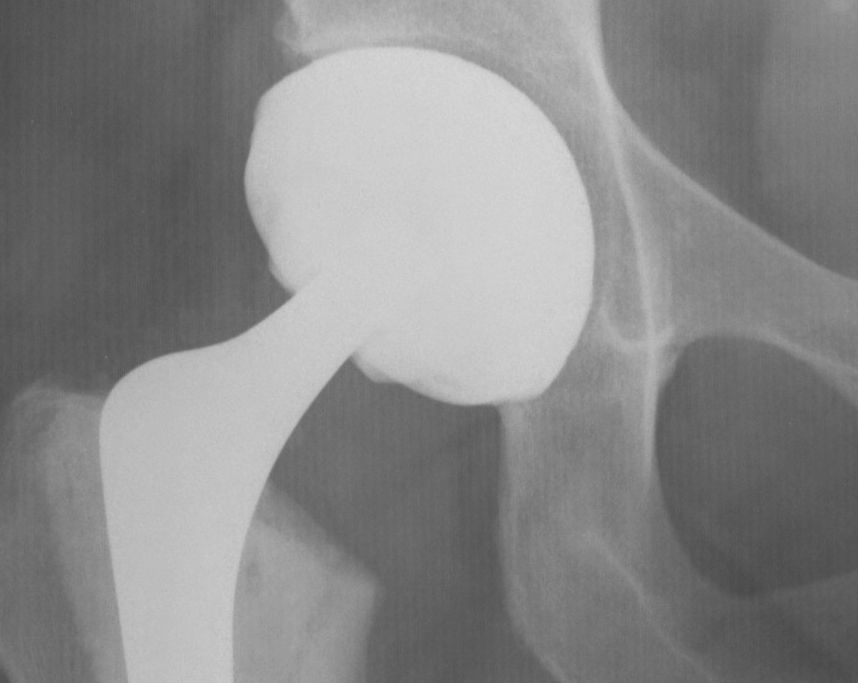

Uncemented Acetabular Component

Concepts

Bone ingrowth into component averages only 12%

- even with 84% bone contact

Non continuous radiolucent lines

- commonly found in press fit acetabular components

- are often not progressive

Radiographic signs of ingrowth fixation

Moore et al CORR 2006

- 3 or more 97% stable

- 2 or less, 83% unstable

Five signs

- absence of radiolucent lines

- presence of a superolateral buttress

- medial bone stress-shielding

- radial trabeculae

- inferomedial buttress

THR Uncemented Cup Superolateral Buttress 2